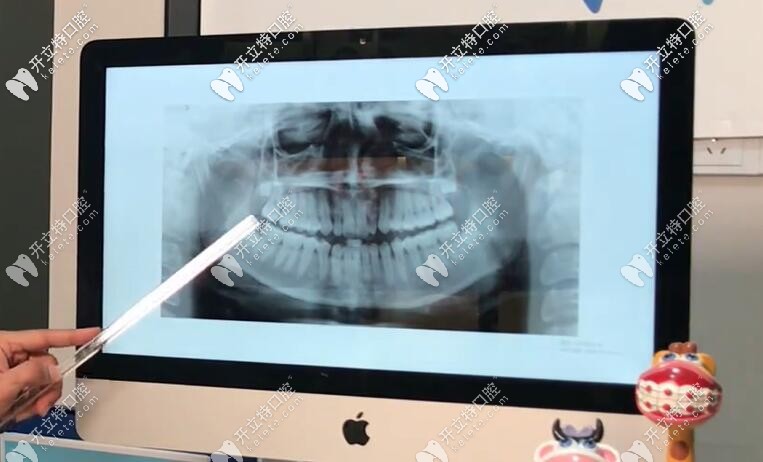

【基本情況】:從圖中(正面)我們可以看出,這個姑娘的下巴有一點歪,但是她的中線上頜還不錯,可是出下巴這邊,她的咬合是不對的,上下頜各有兩顆智齒;

通過x片和國貿(mào)口腔的正畸技術(shù)總監(jiān)Dr.Aref安粵夫的分析后,發(fā)現(xiàn)她有點骨性三類牙齒畸形,她的下巴有點長,地包天牙齒有骨性問題。